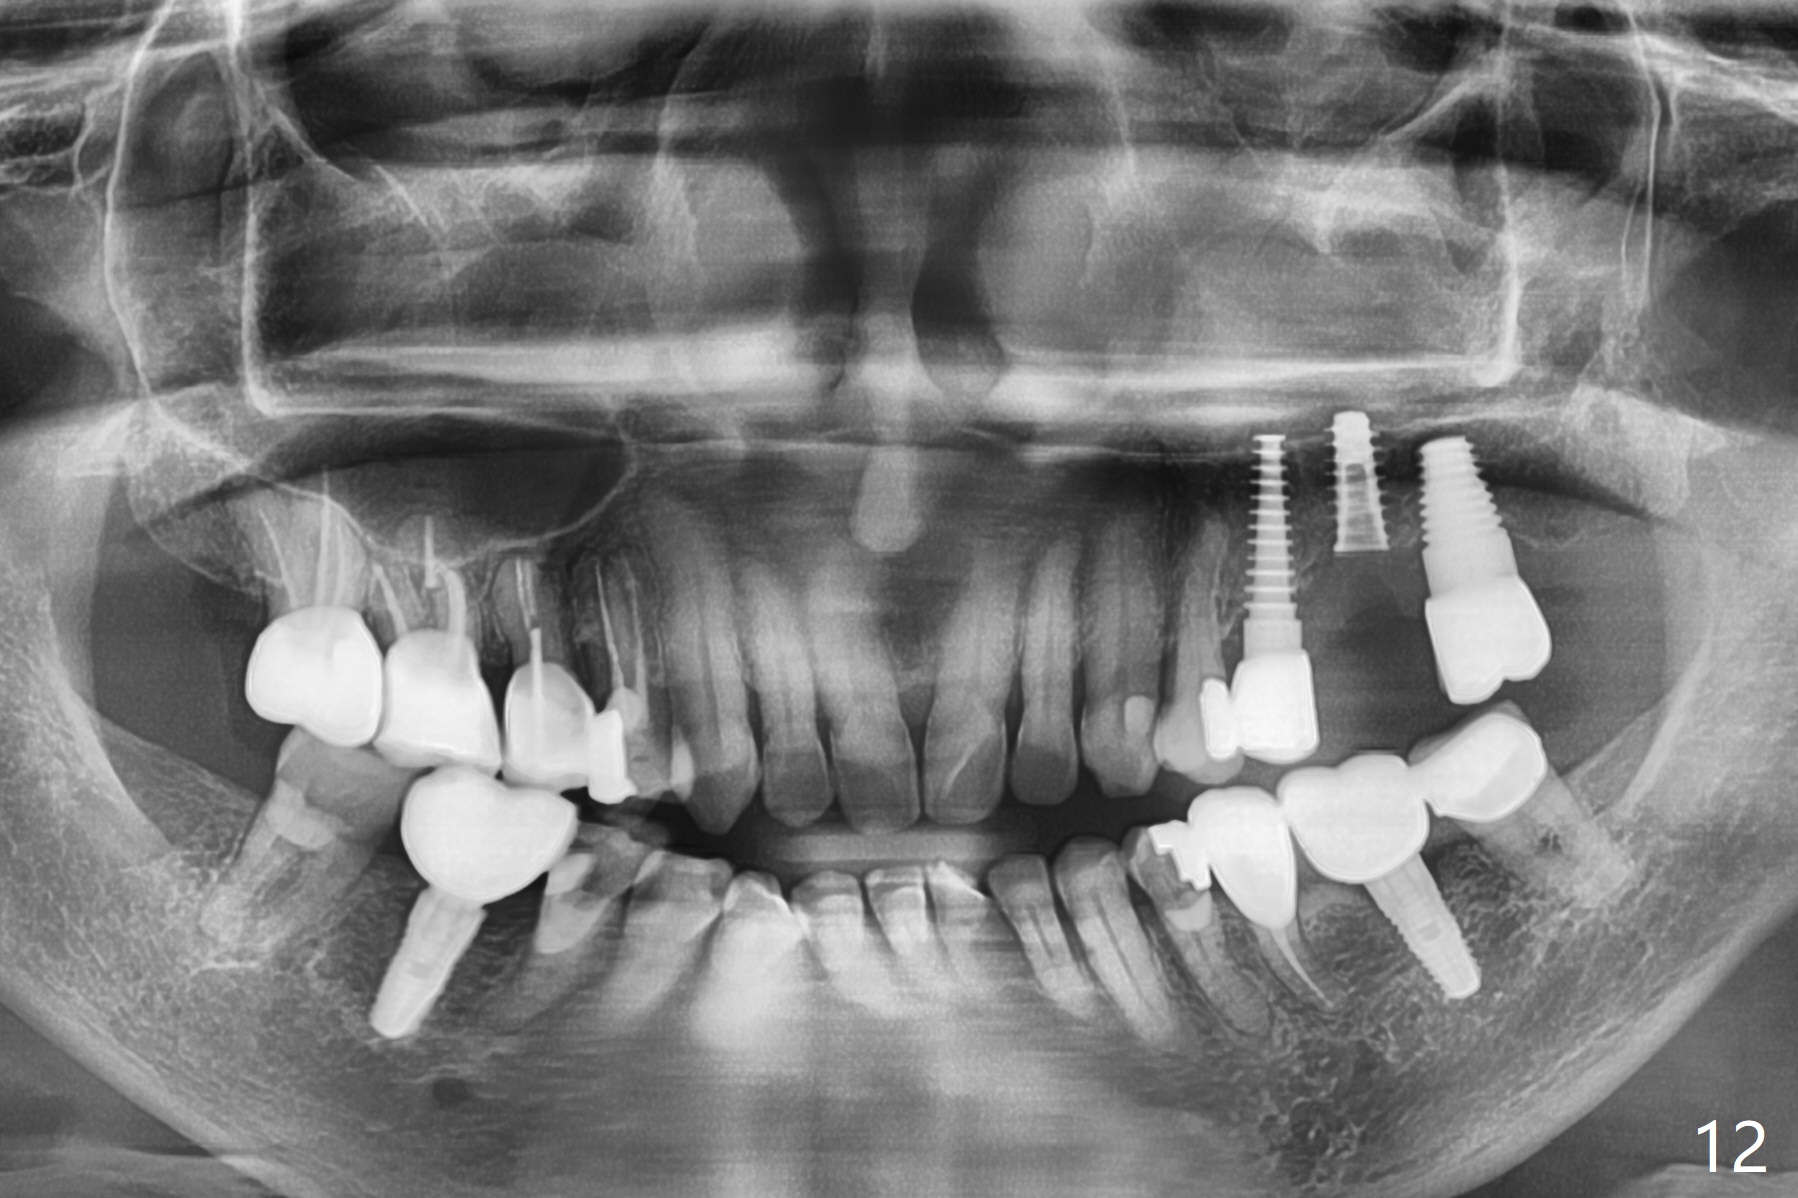

Initial osteotomy in the septum of the tooth #14 is 9 mm, approximately 2 mm from the sinus floor (Fig.1).  Subsequent osteotomy depth is 11 mm, followed by insertion of a 4.5x11 mm dummy implant (Fig.2).  After use of Magic Drill (MD) 4.8 mm for 9 mm, a 5x11 mm IBS implant is placed with sinus lift without additional bone graft (Fig.3 *).  In contrast, autogenous bone (from MD) and Vanilla Graft are meticulously placed in the remaining socket (+) before and after placement of a 6.5x5.7(2) mm abutment.  An immediate provisional is fabricated to close the sockets.  There is buccal tenderness 1-3 months postop.  There is distopalatal implant thread exposure.  A healing abutment (5.5x2 mm) is placed.  CT confirms thin buccal plate (Fig.4,5).  It appears that the implant should have been as palatal as possible.  The tenderness remains for the next 2 weeks.  When the healing abutment is removed, the implant seems to have been placed shallow, ~ 1 mm subgingival (Fig.6).  With local anesthesia, the implant is reversed to clean the coronal threads with Titanium brush and copious irrigation (Fig.7).  The implant is then placed ~4 mm subgingival (Fig.8) and slightly subcrestal (Fig.9,10).  It appears that the postop bone loss (Fig.9 *, as compared Fig.1,2) makes the implant look to be placed too shallow.  When the implant is being placed deeper, the buccal plate feels intact.  The early periimplantitis is apparently due to postop bone loss more than buccal placement, although certain degree of buccal bone resorption must occur.  A 6x4 mm healing abutment is placed.  Left facial swelling develops 2 days post implant elevation (Fig.11,12, as compared to preop (Fig.13)).  The left maxillary sinus cloud (Fig.12) appears to be a false positive finding, since the same feature exists prior to implant elevation (Fig.13).  Both sinuses look clear prior to implant elevation (Fig.14).  Amoxicillin switches to Augmentin and Flagyl, since the patient is reluctant to have the implant removed.  Finally the sinus infection is under control.  The patient feels left facial swelling 9 months postop (5 months post elevation) and reports left nasal discharge ~ 1 month earlier.  There is mild buccal plate tenderness.  The implant seems to be buccally placed (Fig.15,16), although there is no significant change radiographically (Fig.17).  The implant is removed with bone graft (Fig.18 *).  To avoid complication and failure, an immediate implant at the upper 1st molar should be short and placed deep.